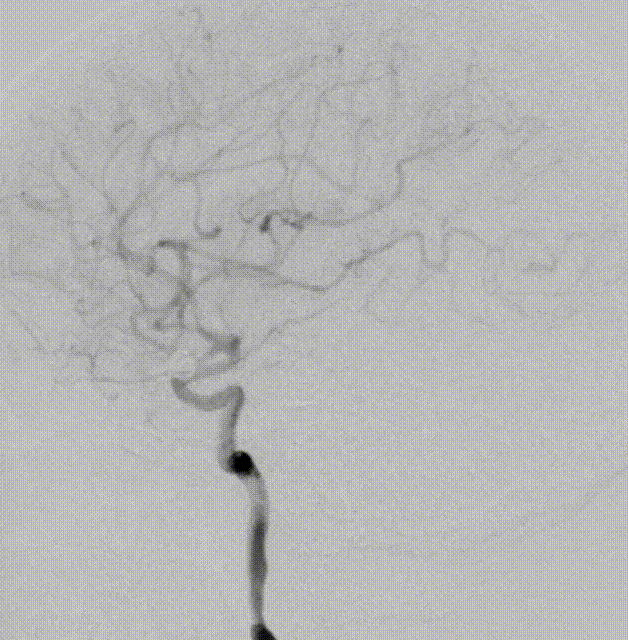

外院DSA

右侧颈内动脉眼动脉段-海绵窦段串联两枚动脉瘤,分别大小约:

① 8.8mm*5.9mm*5.2mm,瘤颈宽7.0mm;

② 6.8mm*4.3mm*3.6mm,瘤颈宽3.3mm。

左侧大脑中动脉分叉处微小动脉瘤大小约2.3mm*1.5mm*1.1mm,瘤颈宽1.7mm(不处理)。